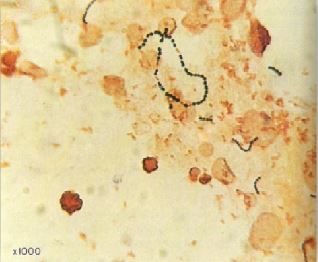

مجموعة من طلبة الكرية العسكرية ظهرت عليهم أعراض التهاب النسيج الخلوي cellulitis على اظهرهم وأذرعهم بعد 24 ساعة من إجراء اختبار التمارين الرياضية . تم اخذ عينة بكشط الجلد للكشف عنها مجهرياً كما في الشكل رقم 1 وزراعتها كما في الشكل رقم 2 .

الشكل رقم 1 : الفحص المجهري

1- هذا الكائن الدقيق عبارة عن البكتريا B- haemolysis streptococcus ويتم تقسيم هذا النوع من البكتيريا اعتماداً على مستضد المواد الكربوهيدراتية المكونة للجدار الخلوي، تسمى المجموعة A من هذه البكتيريا بالنوع البكتيري Streptococcus pyogenes وهو المسؤول عن إصابات الجلد والحلق وكذلك تجرثم الدم ، اما المجموعة B فهي تعرف بالنوع البكتيري Streprococcus agalactiae وهو المسؤول عن الإصابات في المواليد بحيث يسبب مرض التهاب السحايا وتجرثم الدم. والمجموعة C مصدرها الطبيعي الحيوان وهي المسؤولة عن التهاب الحلق والتهاب النسيج الخلوي وكذلك المجموعة G فهي تسبب نفس الأمراض.